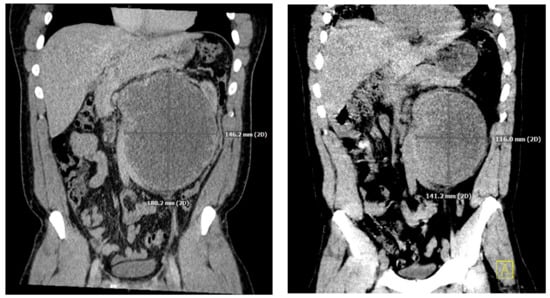

He underwent an orchiectomy of the left testis and received a total of four cycles of etoposide, bleomycin, and cisplatin over the ensuing three months. The tumor was responsive to chemotherapy showing a significant decrease in hCG levels from 75,005 IU/L to 149 IU/L and shrinking of the retroperitoneal mass (Figure 1).

Figure 1.

Coronal slices of CT images performed immediately after diagnosis of retroperitoneal mass (left) originally measuring 18 × 14 cm, and three months after initiation of treatment (right) measuring 14 × 12 cm.

One month after finishing the last cycle of chemotherapy, the patient developed shortness of breath and a dry cough and was diagnosed with pneumonia, requiring readmission to the hospital. His initial oxygen saturation on room air was as low as 90%. He was given supplemental oxygen, ceftriaxone, and azithromycin. A CT scan revealed ground glass opacities and air bronchograms and re-demonstrated his retroperitoneal mass and liver lesion, both significantly smaller (Figure 1 and Figure 2).